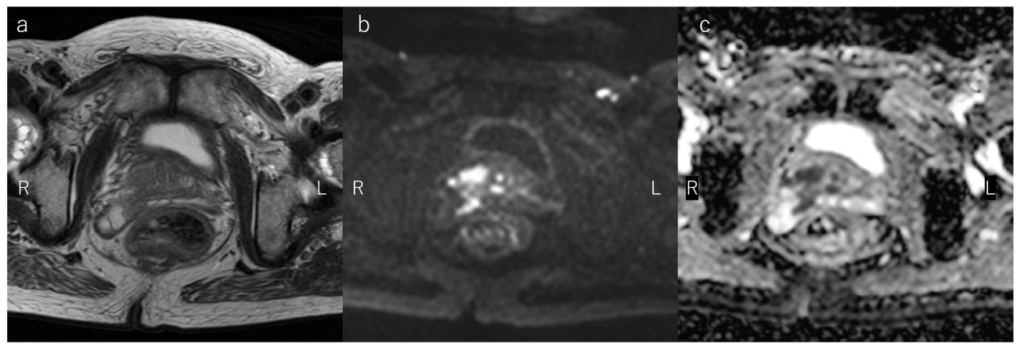

問題 41 前立腺癌疑いで撮像された骨盤部のMRI横断像(a:T2強調像、b:拡散強調像、c:ADCmap)を示す。最も正しい画像所見はどれか。

1. 骨転移

2. 精嚢浸潤

3. 膀胱浸潤

4. 直腸浸潤

5. リンパ節転移